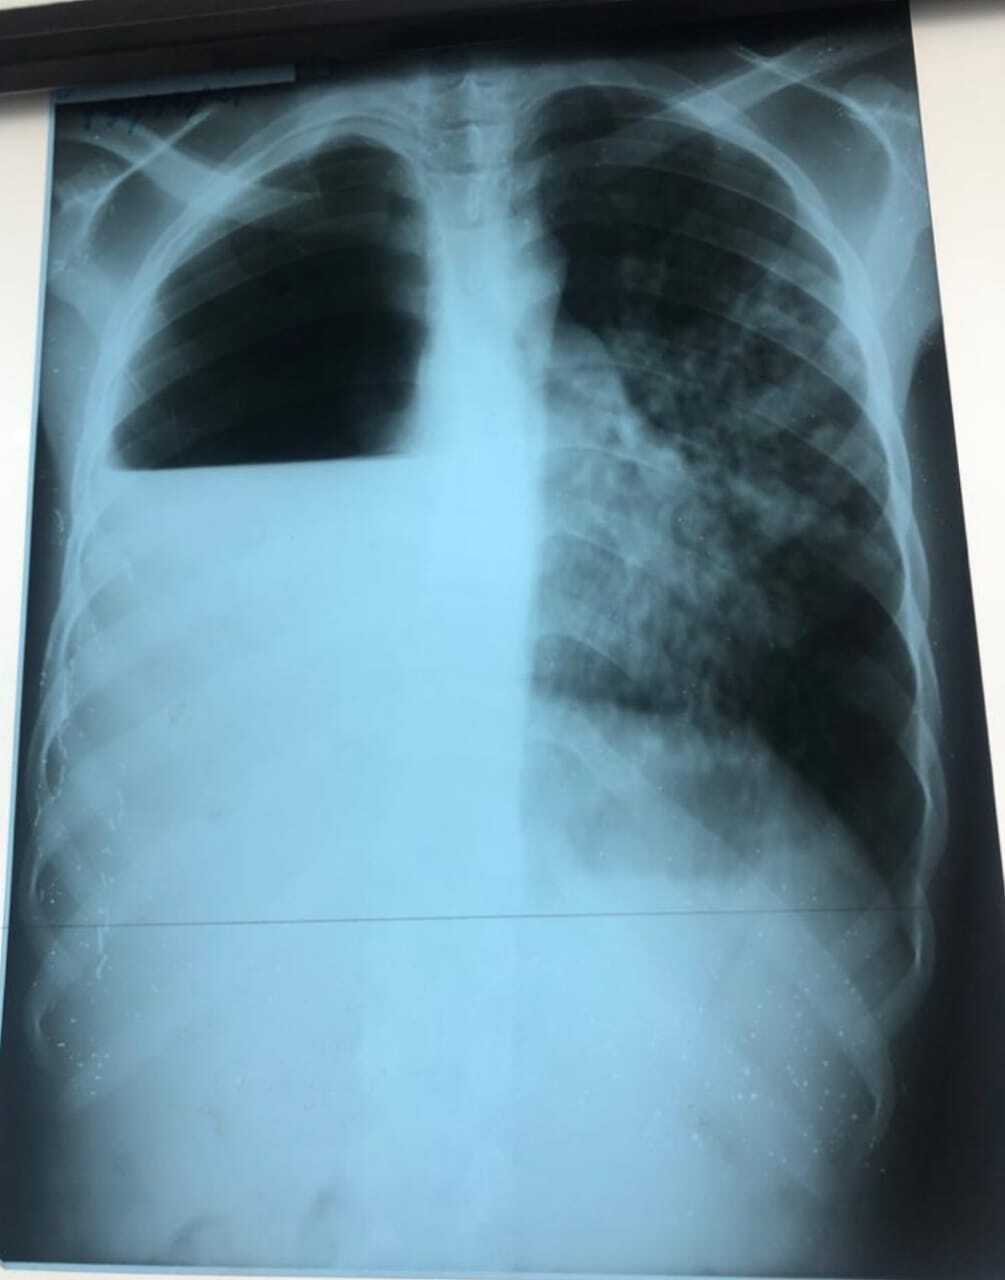

À l’examen : altération de l’état général, associé à une fièvre et sueurs nocturnes ; pâleur cutanéo-muqueuse, PA = 10/60 mmHg, FC = 100 b/min, T°= 38,8 °C, FR = 38 cycles/min, SaO2 : 93 % à l’air ambiant. Syndrome de condensation pulmonaire (râles crépitants) au niveau de l’hémithorax gauche, et syndrome d’épanchement pleural mixte à l’hémithorax droit. Une radiographie du thorax est réalisée aux urgences.

Il s’agit du pyopneumothorax tuberculeux. Explications ci-dessous.

Le pyopneumothorax tuberculeux est une complication rare mais grave de la tuberculose pulmonaire évolutive. Le diagnostic est facilement évoqué quand s’associent au pneumothorax des lésions fibro-cavitaires parenchymateuses. On demande un bilan phtisiologique : recherche de BK (Bacille de Koch) dans les expectorations et dans le liquide d’aspiration bronchique (revenues positifs), IDR (intradermoréaction à la tuberculine : revenu positif), bilan inflammatoire (VS, CRP élevés).